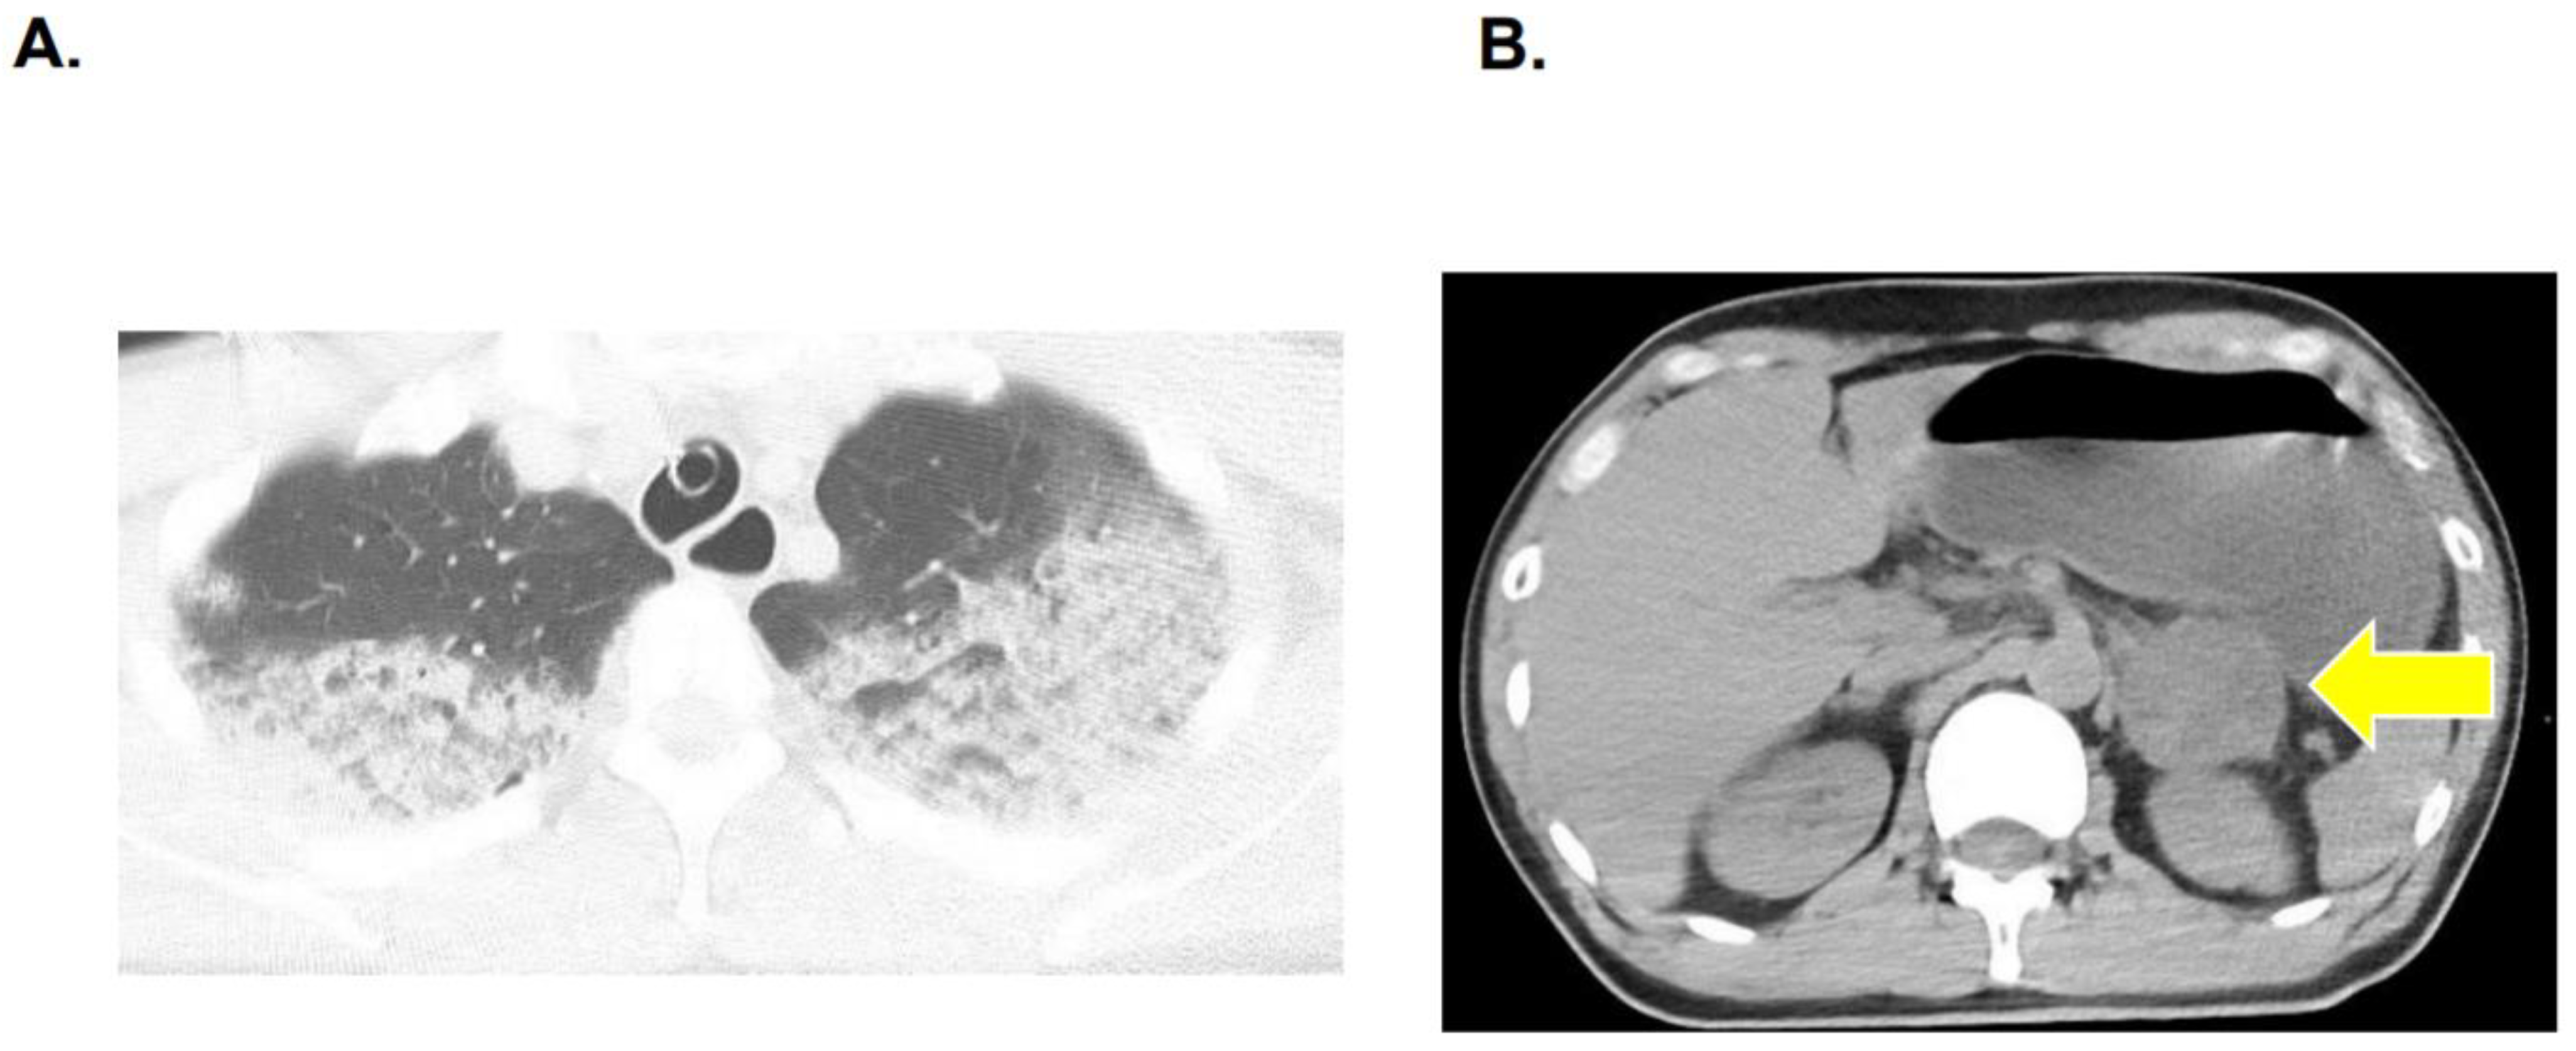

2.5. Diagnosis of Pheochromocytoma and Adrenalectomy